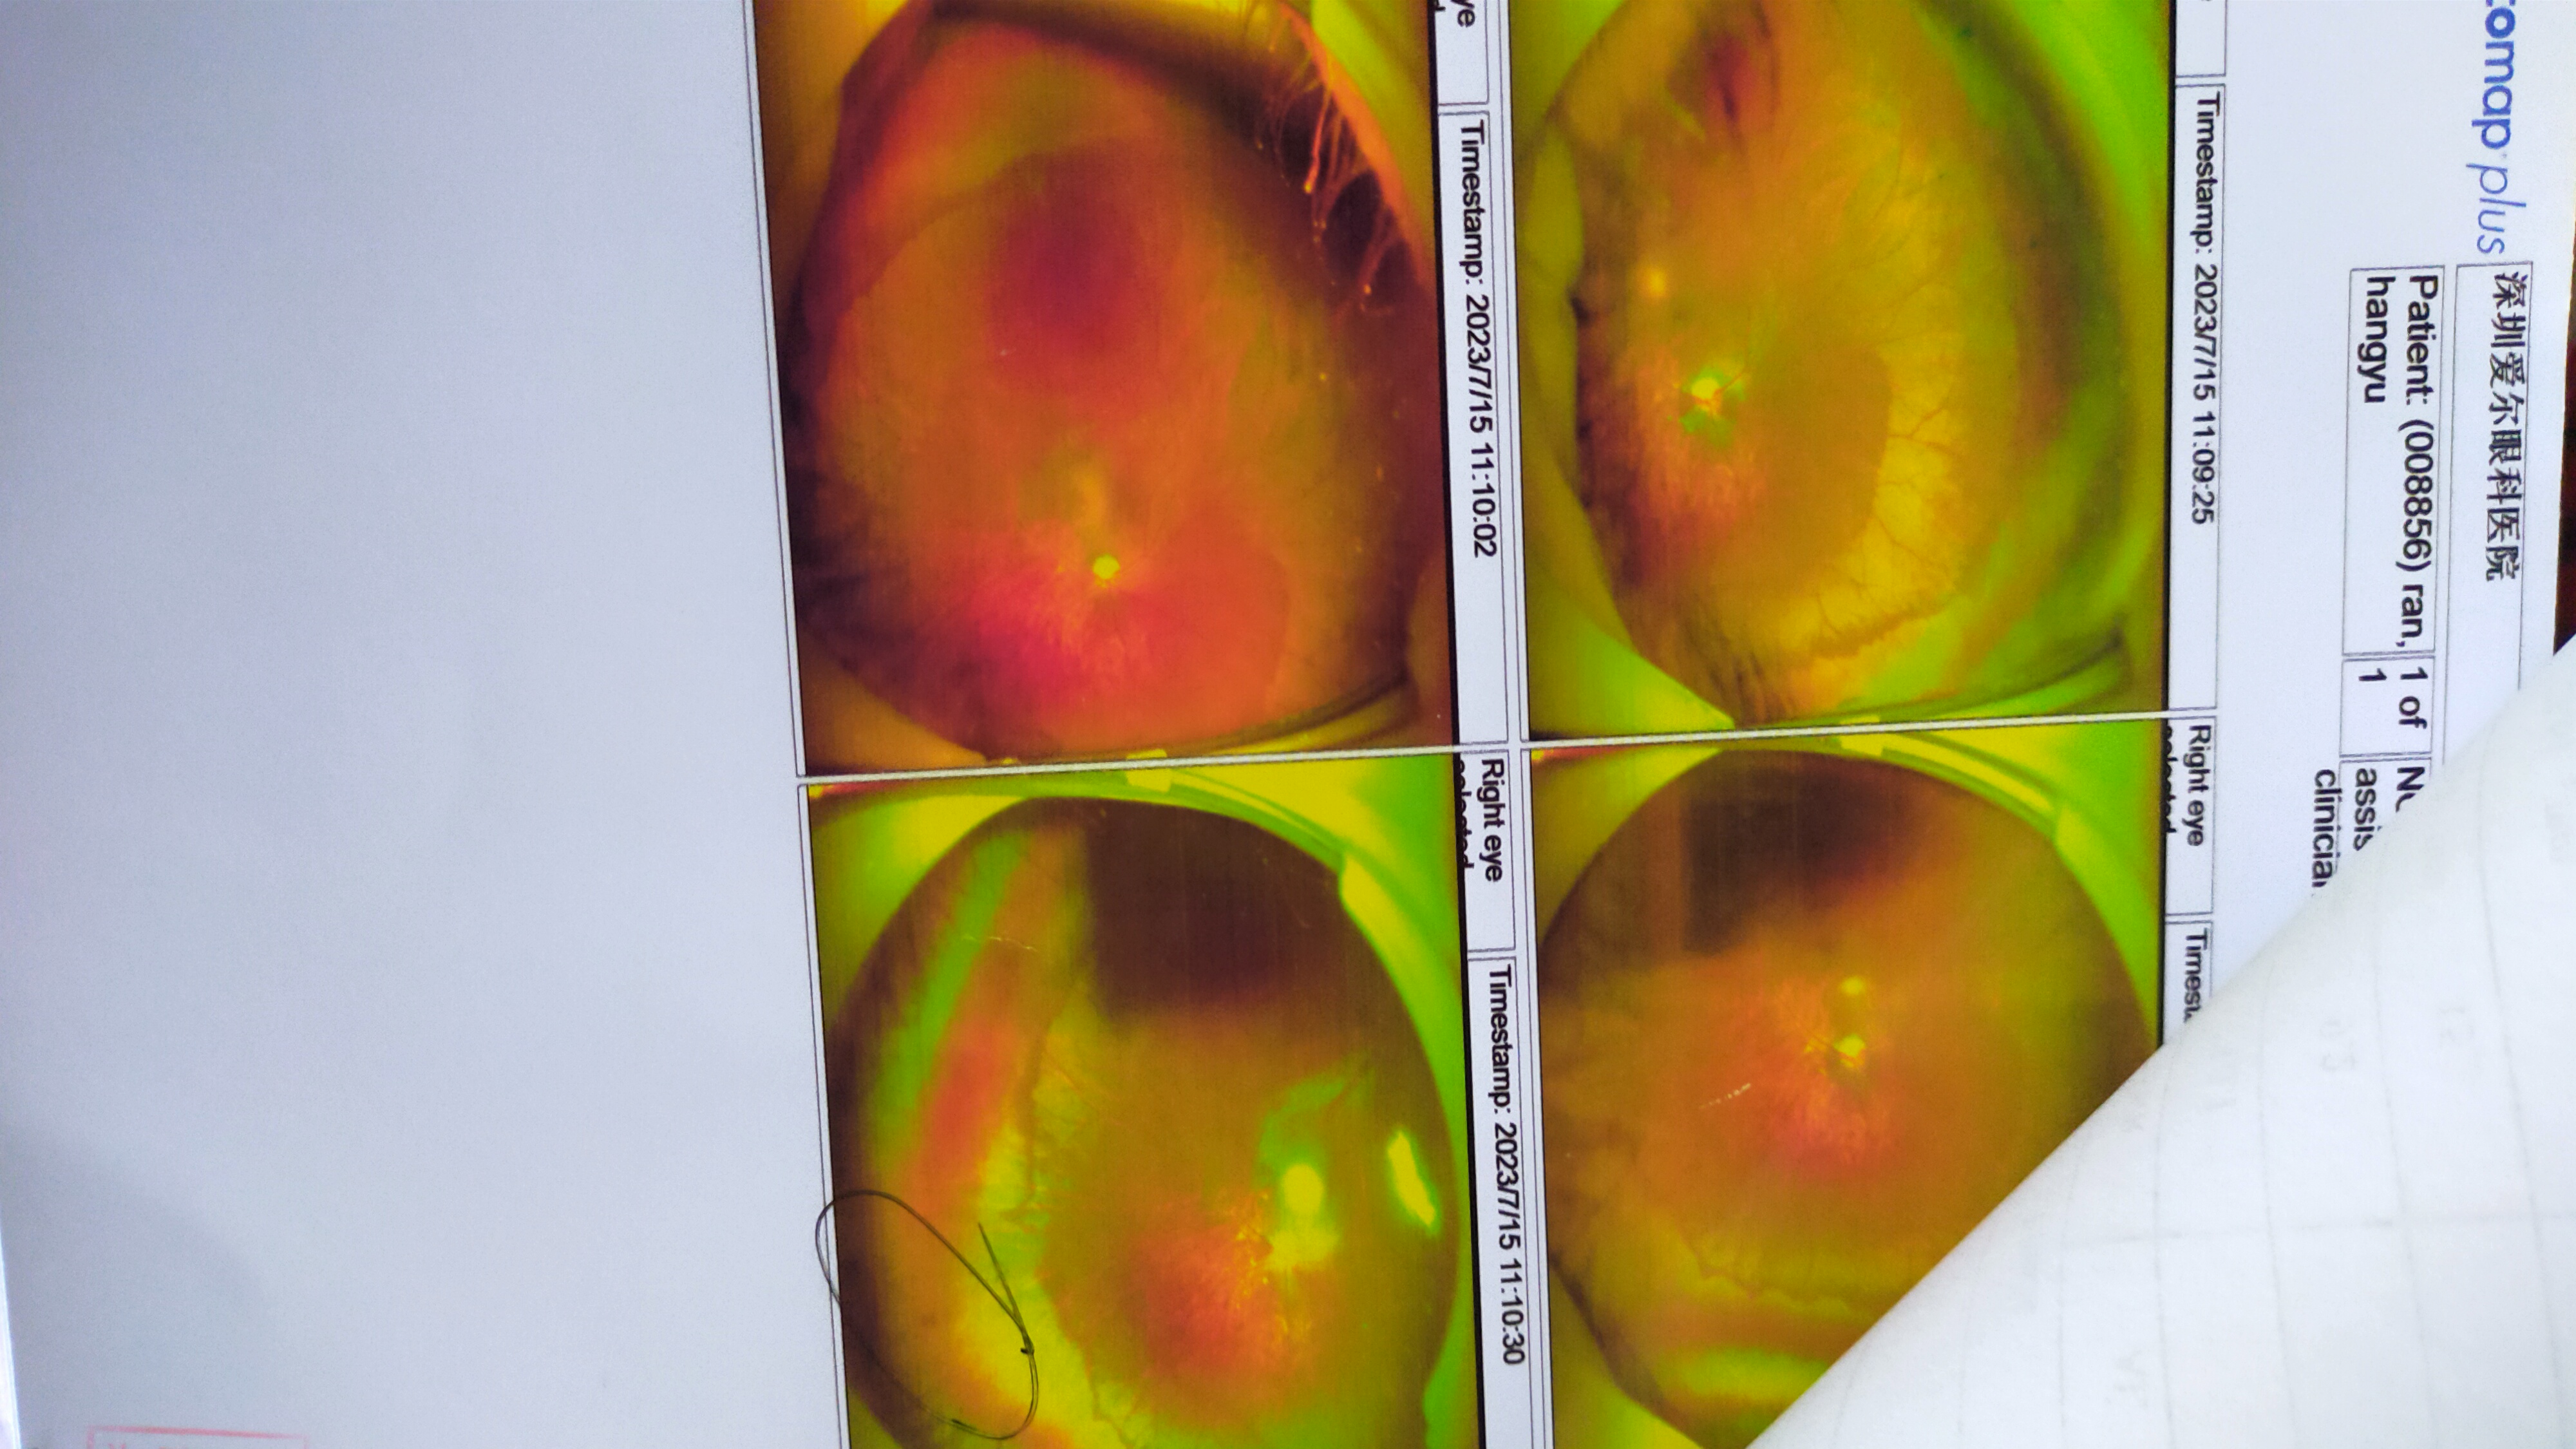

↑2

控轴笔记

斜视巩膜术后20天复查

眼轴各涨 L0.35 R0.23

度数各涨 L75 R50

换镜片

视功能正常,调节力差